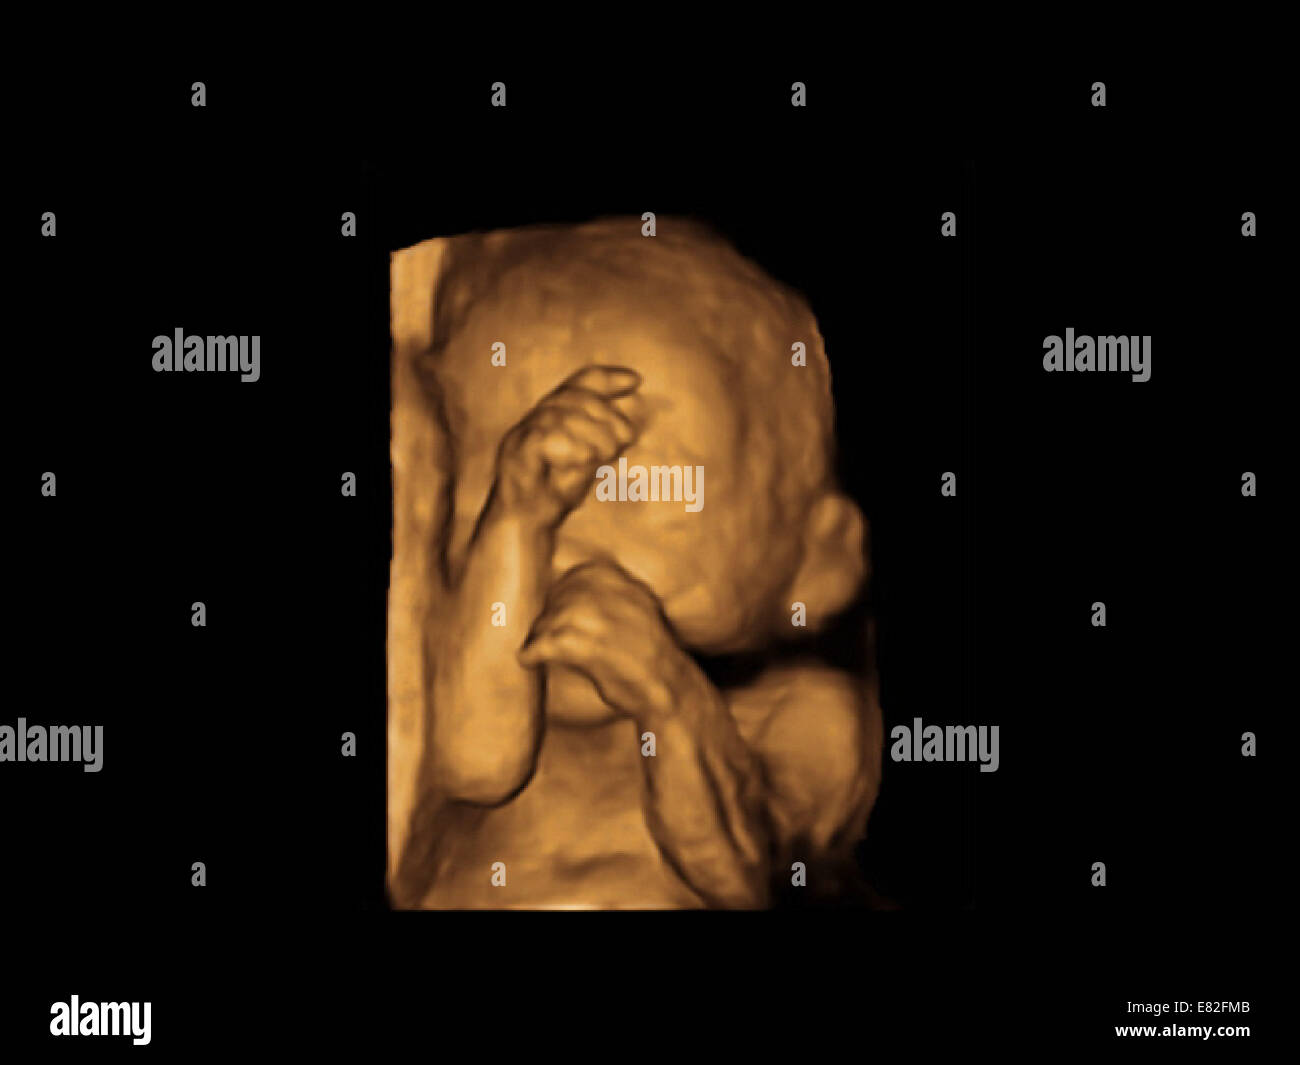

Feto Face Colorati 3 D Di Scansione Ad Ultrasuoni Di Un Feto Eta Gestazionale 22 Settimane E 4 Giorni Foto Stock Alamy

Ecografia Fetale Di 22 Settimane Traguardo Importante Per Il Controllo Delle Condizioni Fetali

Ecografia Tridimensionale 3d E 4d Centro Diagnosi Prenatale